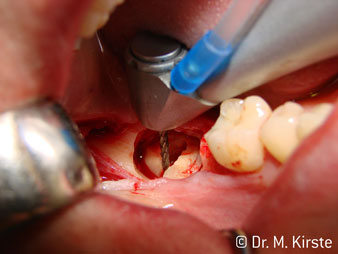

The 45° angle of the handpiece has been specially selected for its wide range of advantages. Colleagues who work in surgery, and for whom this handpiece was primarily developed, will soon appreciate the ability to work efficiently in very restricted spaces. In wisdom tooth extractions in particular (fig. 2) there is no need for large-scale spreading of the soft tissues in the cheek region (fig. 3). The design of the handpiece head combined with turning the head slightly during preparation allows work to be carried out quickly and safely in the retromolar region.

The professional design of the bearings inside the handpiece head guarantees quiet running of the bur; this makes for an impressively atraumatic cut in the separation of tooth and root (fig. 4-9).

Fig. 2